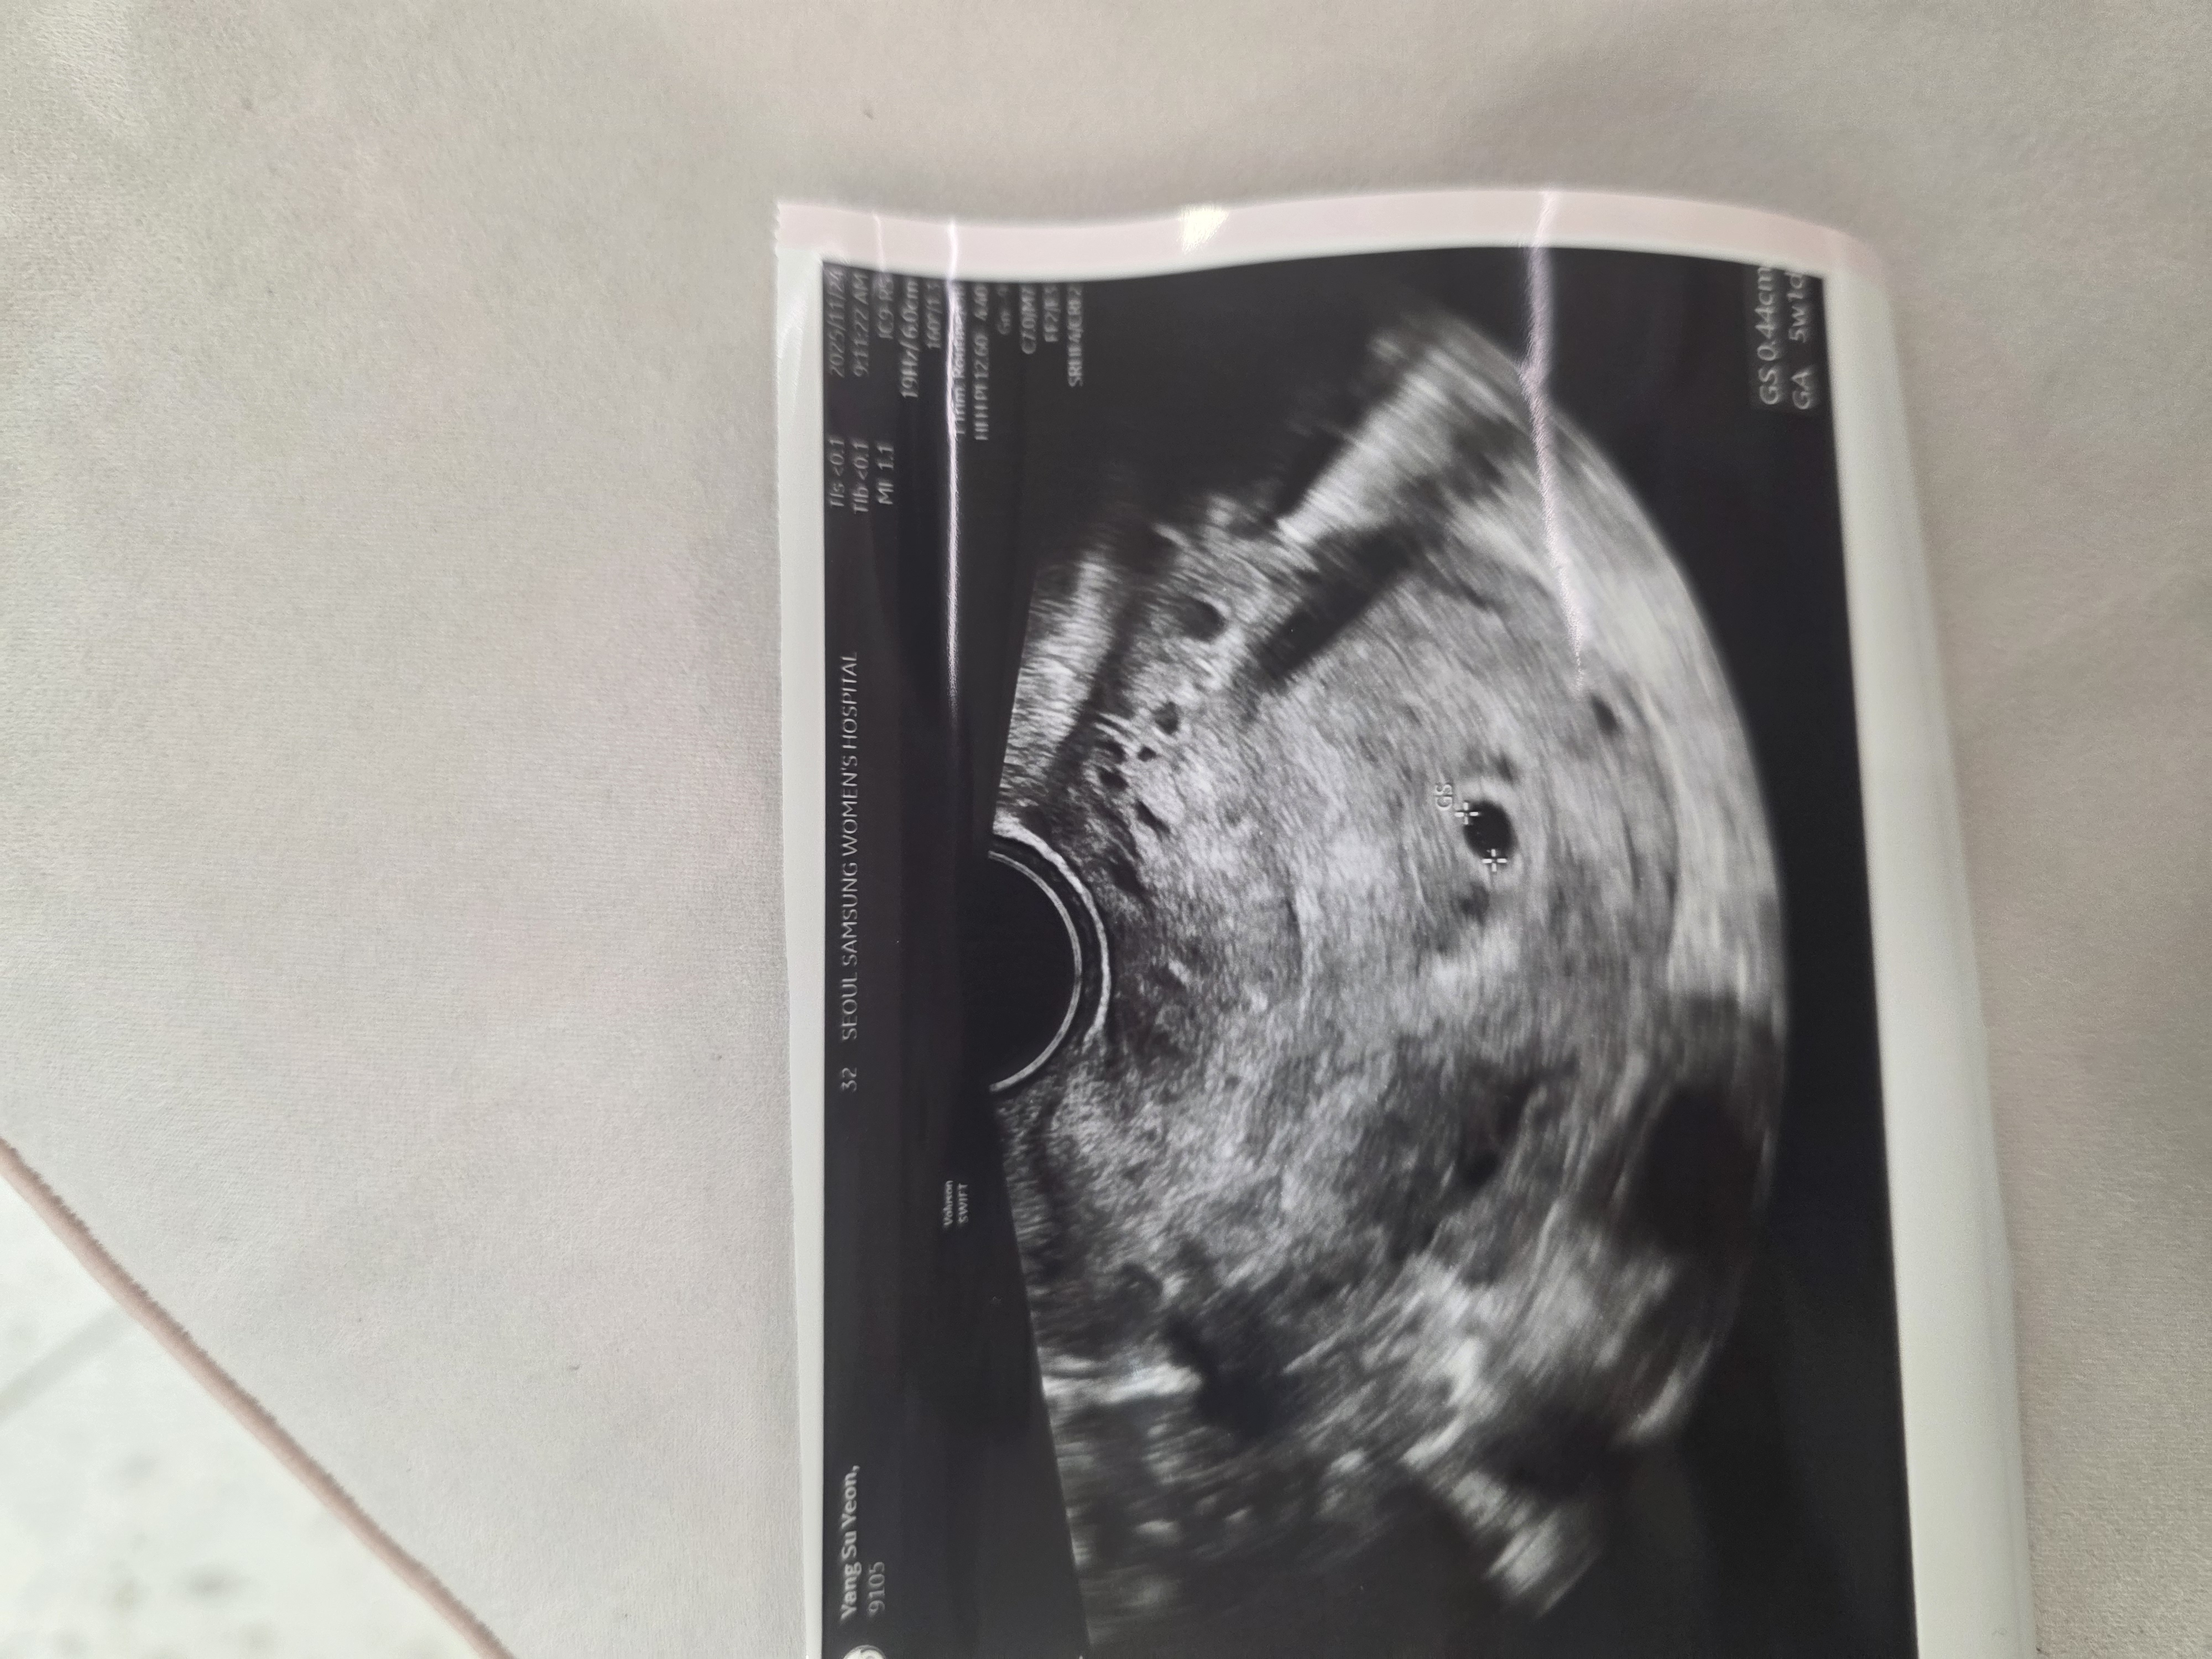

마지막생리시작일 10월8일 배란일 11월1일 배란 23일차 예상 5주2일 가니 5주1일 0.44cm 너무작아 난황도못봤어요 ㅠㅠ 물혹도있고 물고임도있다는데 괜찮을거라는데 걱정되요 ㅠㅠ 배통증도있고..